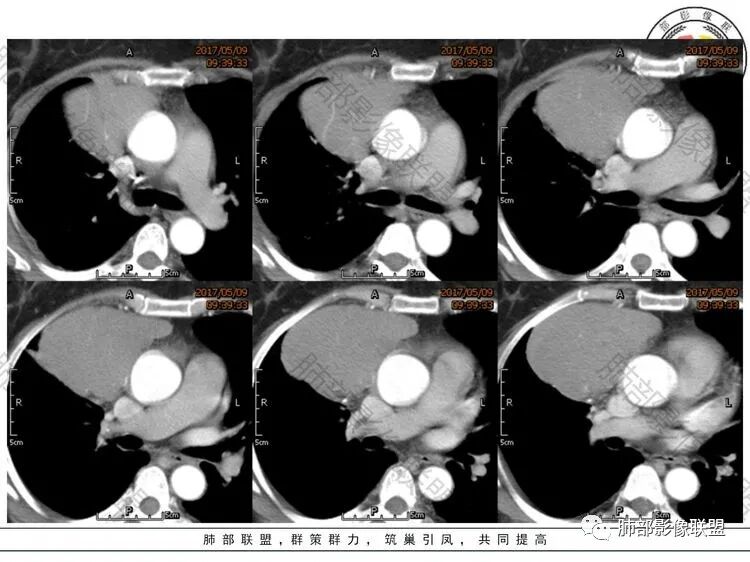

中年女性,体检发现,纵隔前外侧见不规则肿块,内见散在钙化灶,主动脉及心脏受压向后内侧轻度移位,增强后呈均匀性强化,未见明显坏死区,肺动脉延伸其中,轮廓光滑,肿块前外侧见胸膜尾。考虑胸膜来源可能性大,SFT?鉴别胸腺瘤

主要定位,胸膜来源,与纵隔脂肪间隙可见,sft。如果定位纵隔,考虑胸腺瘤。

中年女性,体检,相邻肺组织受压,大部位于右前纵膈,貌似右侧内乳动脉增粗,肿物定位前纵膈,边界清晰,内见线样分隔及钙化,强化均匀!考虑胸腺瘤!

晨读:定位前纵隔偏右侧,病变向右侧突出,形态欠规则,与肺组织交界清楚,右肺受压体积缩小,平扫密度不均匀,可见高密度钙化,增强后可见条状强化,51岁,考虑胸腺瘤囊变,囊性畸胎瘤,鞘瘤囊变

晨读:中年女性,体检发现病变。胸部CT:纵隔右前外侧不规则肿块,内乳动脉供血、胸膜掀起,肺动脉似乎也伸入其中?主动脉及心包受压向内后侧移位,肿块分叶、内见明显分隔、散在点状钙化灶,增强后呈均匀性强化。左侧膈顶有抬高?考虑:胸腺瘤(还是选B2吧)?鉴别SFT、神经源性肿瘤、淋巴瘤等。

胸膜掀起,无胸膜尾征,肺侧肿块光整,纵隔侧肿块分叶,肺动脉供血不可靠,考虑胸腺瘤

中年女性,前纵隔偏侧占位,有分叶、钙化,轻中度强化,似见内乳动脉供血,符合肺外占位,考虑胸腺瘤,鉴别胸膜来源,SFT

晨读:前纵膈占位,分叶,密度均匀,增强轻度强化,其内见钙化,内乳动脉穿行,考虑胸腺瘤AB型。

前纵隔偏右侧肿块,分叶,与心包及大血管间隙尚清晰,其内见分隔及点状钙化,轻度强化,内乳动脉供血,其内见纤细血管,无坏死及囊变,考虑胸腺瘤,AB型